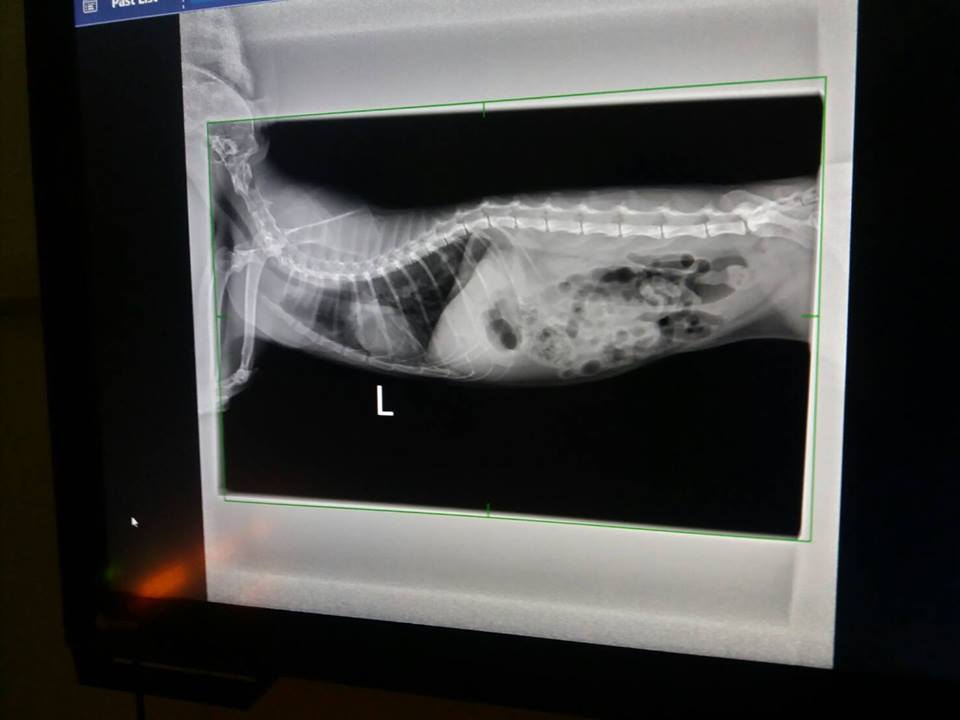

---X光

X光下比較一個月前肺部團塊霧點,

本次已有更清澈,

左側原先擔心是否纖維化的地方,本次有再度散掉一些

右側於上月狀況即有明顯變清澈,本次也有在更改善一些

整體肺部狀況好轉很多